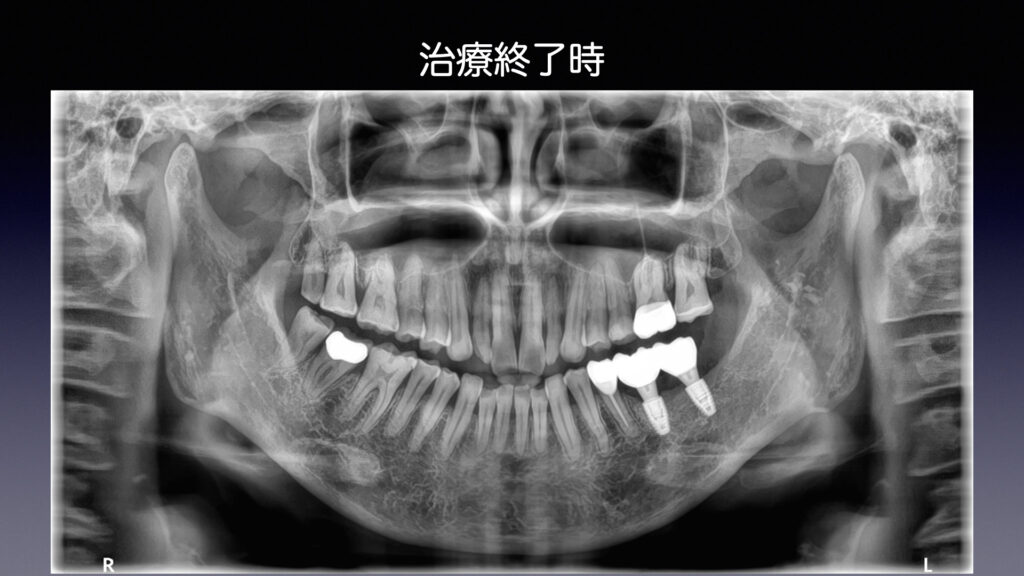

② 過去との比較

治療した当初の状態と比較し、

変化が起きていないかを丁寧に確認します。

初診から治療終了までの流れ